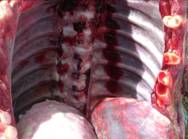

Pleurisy on the surface of the lung or attached to the carcase rib cage